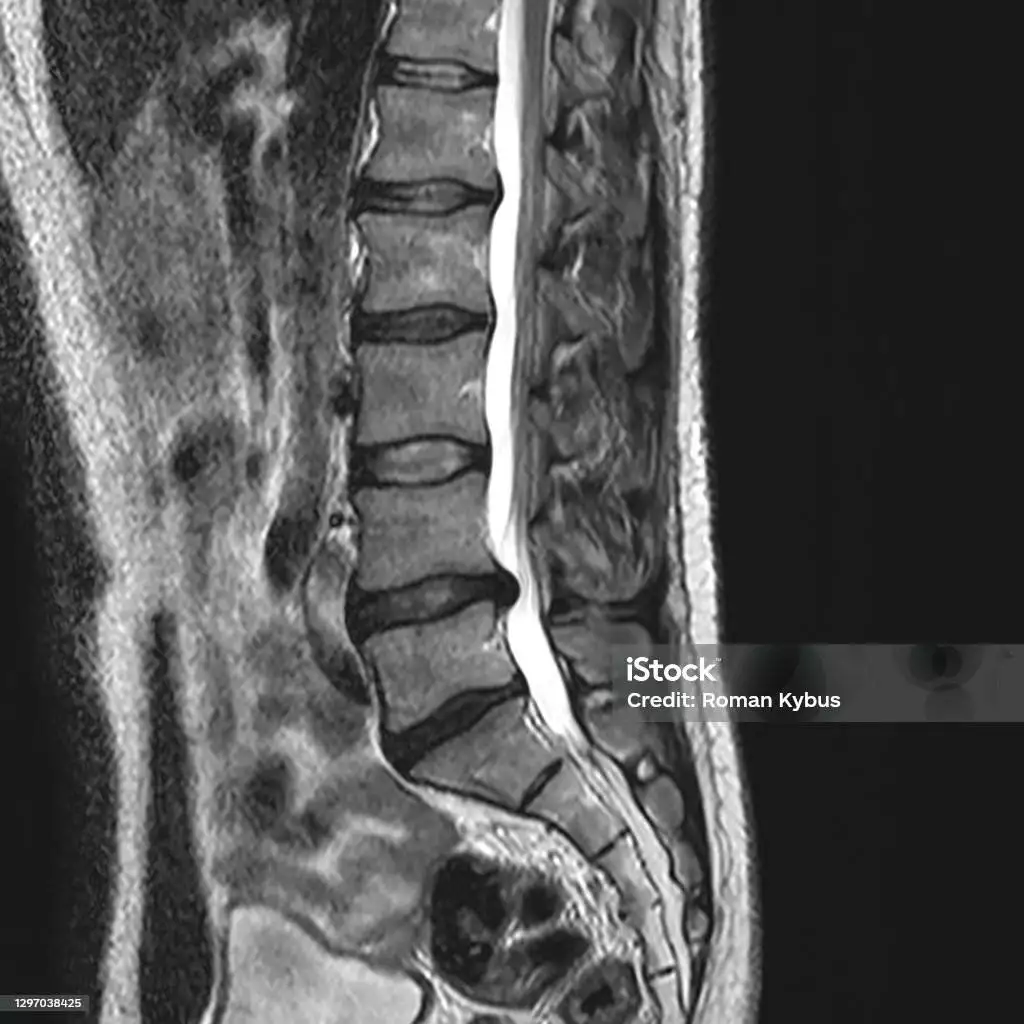

Viele unserer Patienten haben Wirbelsäulenprobleme oder Rückenschmerzen. Die Wirbelsäule ist ein zentraler Bestandteil des Bewegungsapparates. In unserer Gesellschaft beträgt die Wahrscheinlichkeit, im Laufe des Lebens an Rückenbeschwerden zu leiden, über 80%. In den seltensten Fällen ist eine Operation notwendig. Schmerzen im Rücken können lokal vorhanden sein oder in andere Körperregionen (Arme, Beine Kopf) ausstrahlen. Neben strukturellen Schädigungen sind häufig muskuläre Dysbalancen sowohl für akute als auch chronische Beschwerden verantwortlich. Wir führen bei Rückenproblemen eine umfassende Diagnostik durch. Dabei legen wir Wert auf ausführliche Befundung. Die Behandlung wird dabei immer individuell auf den Behandlungsfall abgestimmt, ein angepasster Behandlungsplan mit unseren Patientinnen/-en besprochen und die Therapie gemeinsam festgelegt.

Bandscheibenvorfall

Nicht immer aber häufig geht ein Bandscheibenvorfall mit akuten Rückenschmerzen einher und strahlt je nach Höhe des Wirbelsäulensegments in Arme oder Beine aus. Bei starken Schmerzen, Lähmungserscheinungen oder Mißempfindungen besteht der Verdacht, dass eine Bandscheibe die empfindlichen Nerven einengt oder schädigt.Meist reicht eine zielgerichtete und konsequent durchgeführte konservative, also nicht-operative Therapie zur Besseung der Beschwerden aus.

Hier kommen verschiedene Therapieoptionen in Betracht, wie unter anderem Physiotherapie, Akupunktur, Kinesio-Tape und gezielte Injektionen (PRT mit Kortison). In weniger als zehn Prozent der Fälle wird eine Operation notwendig.